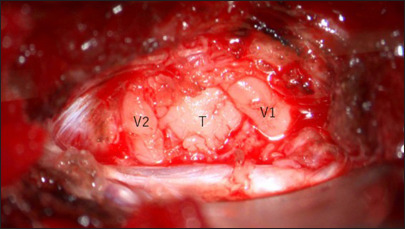

Case description: A case of a 42-year-old woman presented with facial numbness and headache. Magnetic resonance imaging revealed a 25-mm enhancing mass in the left Meckel cave, initially suspected to be a trigeminal schwannoma. Craniotomy and tumor resection were performed. Intraoperative findings and rapid pathology indicated marked inflammatory cell infiltration without features of schwannoma. The final diagnosis was inflammatory pseudotumor, with no evidence of IgG4-related disease or malignancy. Postoperative symptoms improved, and only a short course of steroids was administered.